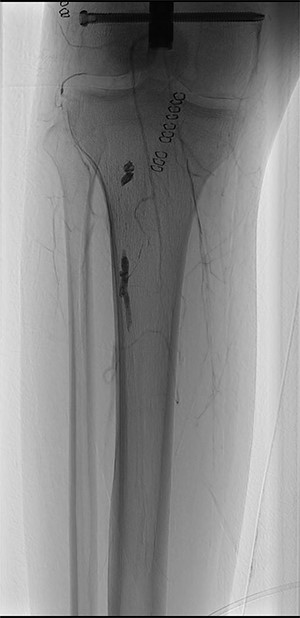

During hospitalization, the patient underwent many orthopedic surgeries for various fractures of the right lower limb, and a centimetric pseudo-aneurysm of the right SFA (Fig. 1), was found at a routine duplex ultrasound of the lower limbs, originating from a small collateral branch of SFA at the distal third of the thigh.

Preoperative angiography showing the pseudo-aneurysm of the right SFA, originating from a small collateral branch of SFA at the distal third of the thigh.

The consultant interventional-radiologist indicated the need for an endovascular repair of the lesion. Through percutaneous puncture of the left common femoral artery, selective catheterization of the right SFA was performed, and embolization of the pseudoaneurysm and the tract of the artery downstream of it, was completed with ONYX 34.